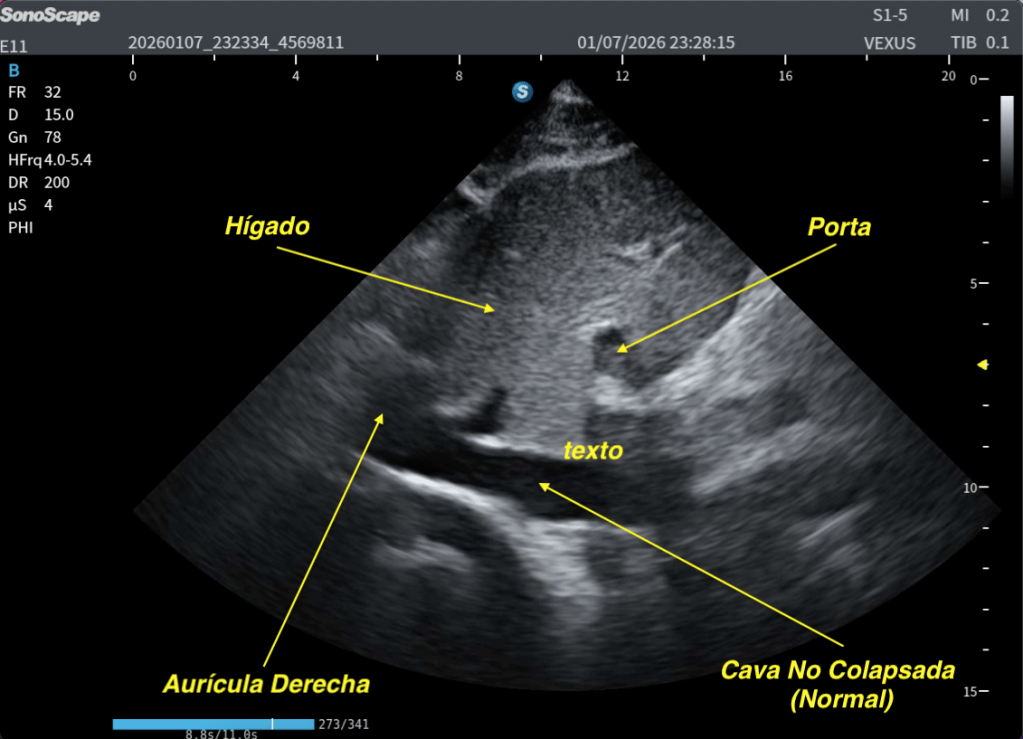

Te lo explico en las dos siguientes imágenes:

✅Normalidad de la Cava con el SNIF.

Esta maniobra demuestra, en este caso, normalidad.